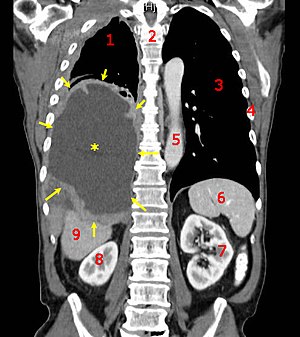

Mesothelioma is a rare cancer linked to asbestos exposure that attacks the lining of the organs – lung, heart and abdomen. The most common is malignant pleural mesothelioma or cancer of the lining of the lungs. Mesothelioma has a long latency period and symptoms are non-specific, so in most cases diagnosis is difficult before the advanced stages of the disease. Typical mesothelioma treatment includes chemotherapy, surgery and radiation in an effort to extend the patient’s life.